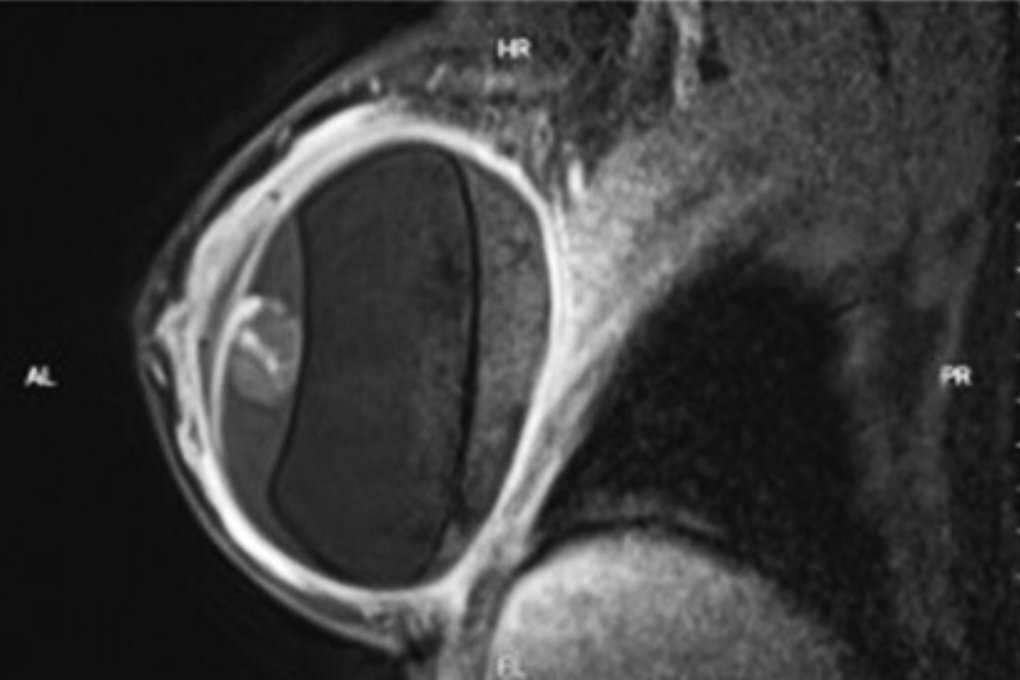

Người phụ nữ được chỉ định siêu âm và chụp cộng hưởng từ (MRI), ghi nhận túi ngực bên trái có tụ dịch.

Ảnh chụp MRI của một bệnh nhân gặp biến chứng sau khi đặt túi ngực (Ảnh: BV).